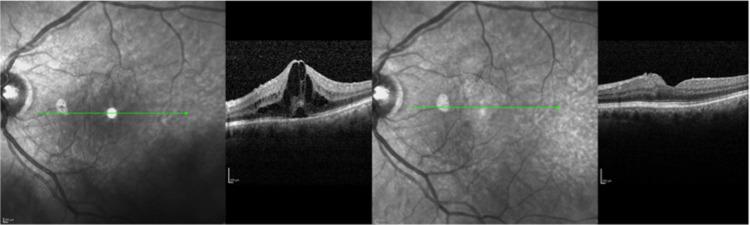

In this prospective, clinic-based, non-randomized case-series, 21 patients (21 eyes) were enrolled with either acute or chronic postoperative CME after cataract extraction. Patients were treated with twice-daily nepafenac 0.3% drops, and followed for at least a 4-month period. Best-corrected visual acuity (BCVA) and spectral-domain optical coherence tomography (SD-OCT)-derived central retinal thickness (CRT) were measured.

From 21 patients, eight presented with acute postoperative CME and 13 with chronic CME. Mean follow-up was 4.82±1.24 months. No adverse events were reported during the study. Baseline BCVA was 0.49±0.36 logMAR and improved to 0.36±0.42 logMAR at the last follow-up visit (<0.005). CRT decreased from 450.40±90.74 μm at baseline to 354.60±81.49 μm (<0.05), following treatment.

在这项前瞻性、基于临床的非随机病例系列研究中,纳入了21例白内障摘除术后出现急性或慢性CME的患者(21只眼)。患者接受0.3%奈帕芬酸滴眼液每日两次治疗,并随访至少4个月。测量最佳矫正视力(BCVA)和光谱域光学相干断层扫描(SD-OCT)得出的中心视网膜厚度(CRT)。

21例患者中,8例出现急性术后CME,13例出现慢性CME。平均随访时间为4.82±1.24个月。研究期间未报告不良事件。基线BCVA为0.49±0.36 logMAR,在最后一次随访时提高至0.36±0.42 logMAR(<0.005)。治疗后,CRT从基线时的450.40±90.74μm降至354.60±81.49μm(<0.05)。